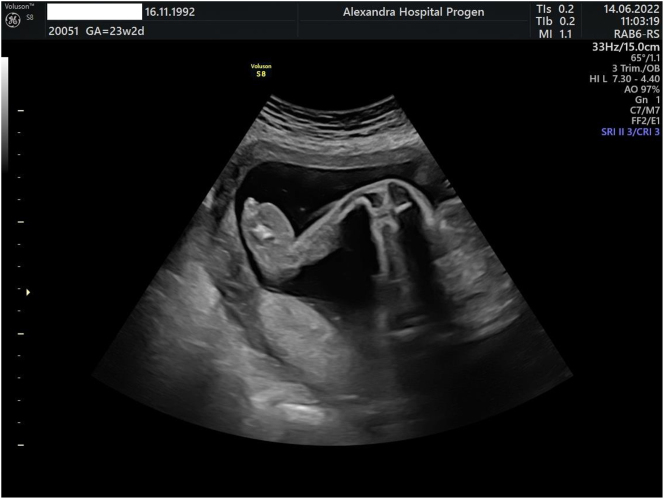

Case presentation: We present a case report of a first-described mutation of a male fetus diagnosed prenatally with Milroy syndrome through amniocentesis. The fetus had bilateral lower limb edema, and genetic testing confirmed the diagnosis of Milroy syndrome. The patient was closely monitored throughout the pregnancy, and after delivery, the infant was managed with appropriate therapies, including compression garments and manual lymphatic drainage. The parents were provided with appropriate counseling and support.

Abstract Image